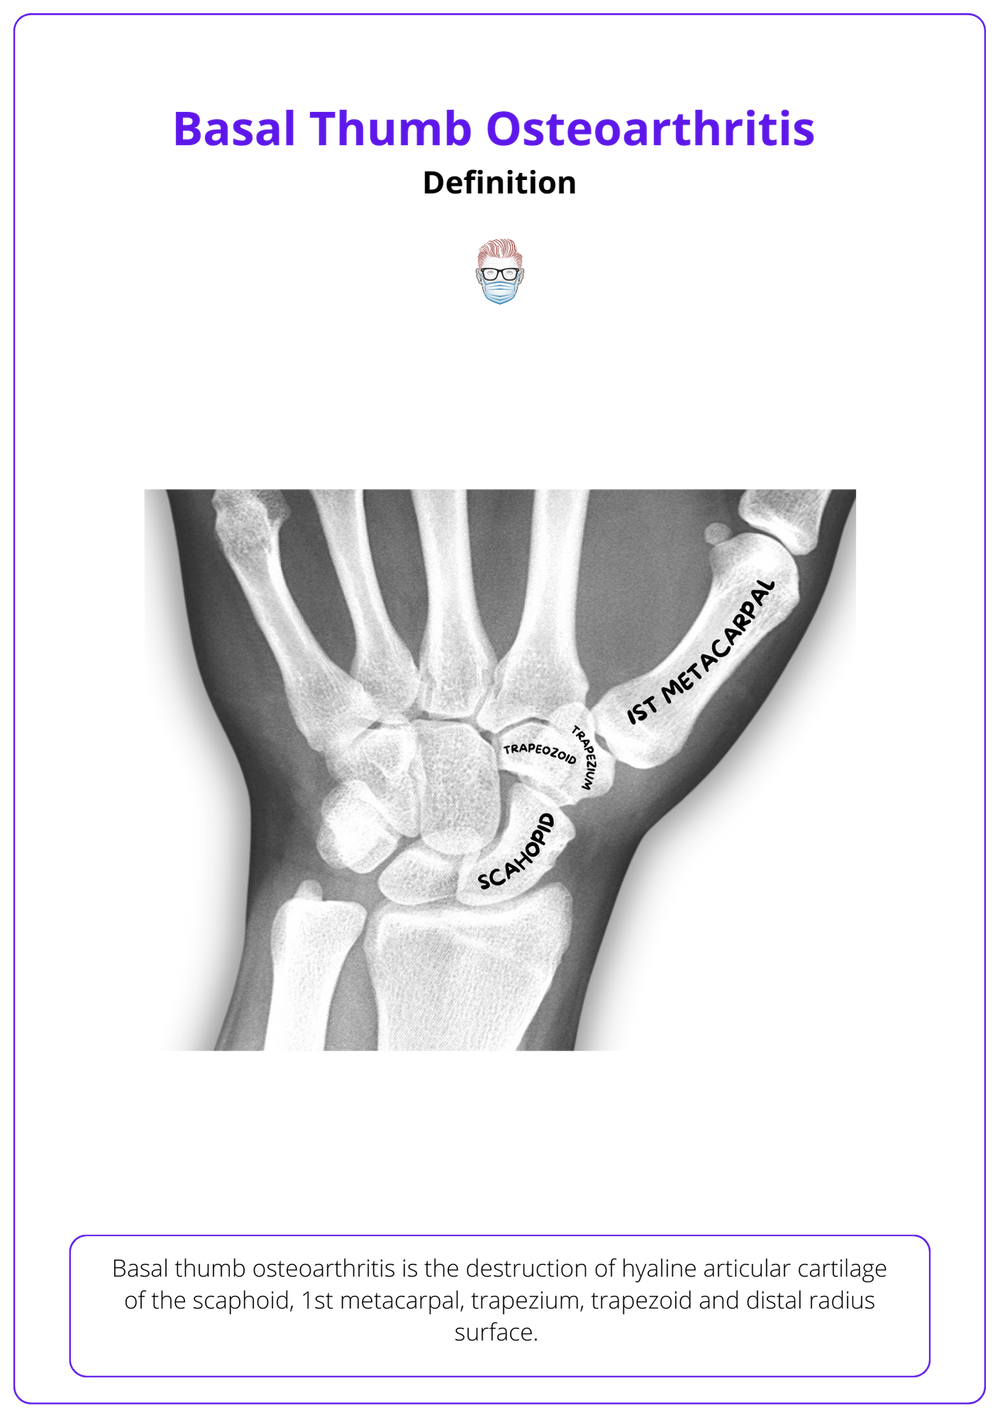

Cmc (Basal Joint) Osteoarthritis. the basal joint at the base of the thumb — or thumb cmc joint — is located near the wrist and at the fleshy part of the thumb. up to 15% of the population older than 30 years suffers from symptomatic thumb carpometacarpal. in your thumb, osteoarthritis develops most often in the basal joint at the base of your thumb. This is also called your thumb. Symptoms can include pain and swelling. This leads to symptoms such as pain, swelling, and stiffness in the affected joint. the universal joint at the base of the thumb, between the metacarpal and trapezium bones, often becomes arthritic as people get older. osteoarthritis (oa) happens when the tissue that helps cushion a joint breaks down over time. basilar thumb arthritis, also referred to as trapeziometacarpal (tmc) arthritis, is a common degenerative. carpometacarpal osteoarthritis is also known as osteoarthritis of the thumb or cmc joint arthritis. Treatment typically includes icing, splinting, and.